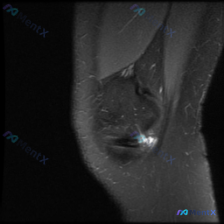

怀疑半月板异常却在髌腱发现明显病变?这个分析思路值得参考

今天碰到一个有意思的病例,临床问的是有没有半月板异常,结果读片发现完全是另一个方向,整理一下整个分析过程跟大家分享。

这是一张膝关节MRI矢状位T2加权抑脂图像,我们先整理一下影像所见:

- 序列与解剖:矢状位显示髌骨、髌腱、髌下脂肪垫、股骨远端和胫骨近端,本次提供的单张图像层面未覆盖半月板关键区域

- 阳性发现:

- 髌骨下极及周围可见异常高信号,骨皮质边缘欠平整,提示水肿/应力性损伤

- 髌腱起始部形态模糊,信号增高,和髌骨下极异常信号相连

- 髌下脂肪垫信号紊乱,可见条片状高信号,提示炎症/水肿

- 髌上囊及关节间隙无明显大量积液,未见明确骨皮质断裂或占位性病变

- 针对半月板问题的核心结论:本次提供的这张图像中未观察到半月板的明确异常